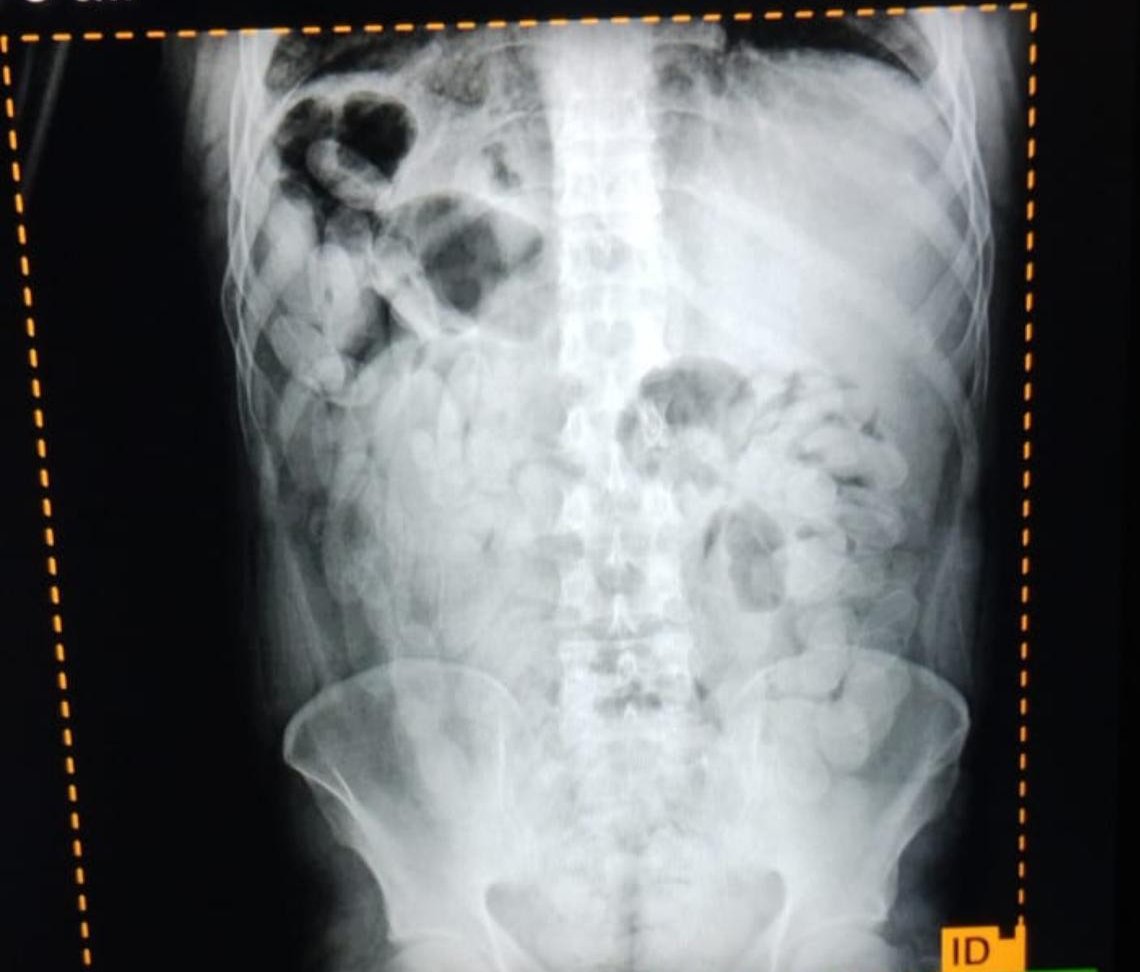

Ante las altas posibilidades de estar frente a la modalidad de traslado de estupefacientes denominada "capsulero" y para preservar la salud de las personas, se solicitó asistencia de emergencia y el traslado al Nosocomio local, en donde mediante placas radiográficas pudieron confirmar la presencia de capsulas.

Luego, los involucrados evacuaron 180 capsulas que sometidas a la prueba de campo narcotest dieron resultado positivo para cocaína con un peso total de 2 kilos 102 gramos.